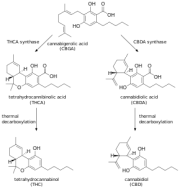

| 03:16, 4 במרץ 2024 | Cannabidiol 1.png (קובץ) |  |

8 קילו־בייטים | Motyk | 1 | |